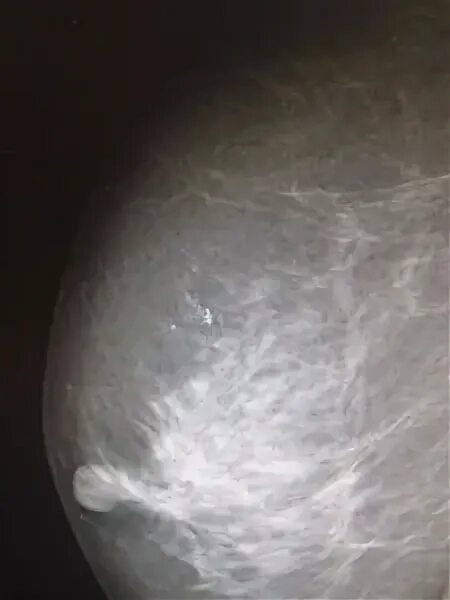

Микрокальцинаты отзывы